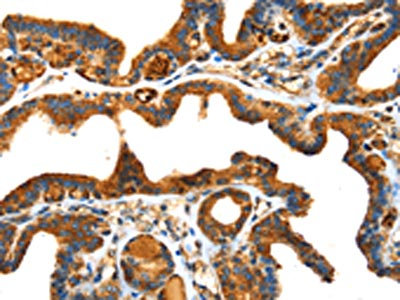

The image on the left is immunohistochemistry of paraffin-embedded Human liver cancer tissue using CSB-PA785325(SPARC Antibody) at dilution 1/25, on the right is treated with fusion protein. (Original magnification: ×200)

The image on the left is immunohistochemistry of paraffin-embedded Human thyroid cancer tissue using CSB-PA785325(SPARC Antibody) at dilution 1/25, on the right is treated with fusion protein. (Original magnification: ×200)